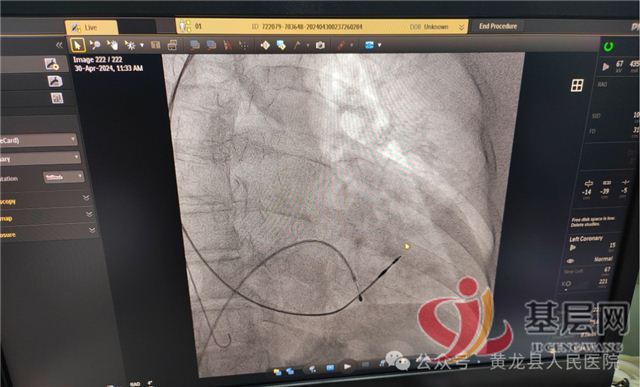

患者高某,女,68岁,以“发作性胸闷、气短6年,加重3天”入院,入院诊断:冠状动脉粥样硬化性心脏病 稳定型心绞痛,造影检查提示一支血管严重狭窄,在介入手术室顺利植入支架1枚。

患者袁某,女,77岁,以“间断胸闷、气短40年,加重10天”入院,入院诊断:冠状动脉粥样硬化性心脏病 不稳定型心绞痛,造影检查提示:一支血管严重狭窄,在介入手术室顺利植入支架2枚、药物球囊1枚。

患者胡某,女,57岁,以“胸痛3小时”就诊于急诊科,诊断胸痛待查,经急诊冠脉造影检查排除心源性胸痛。